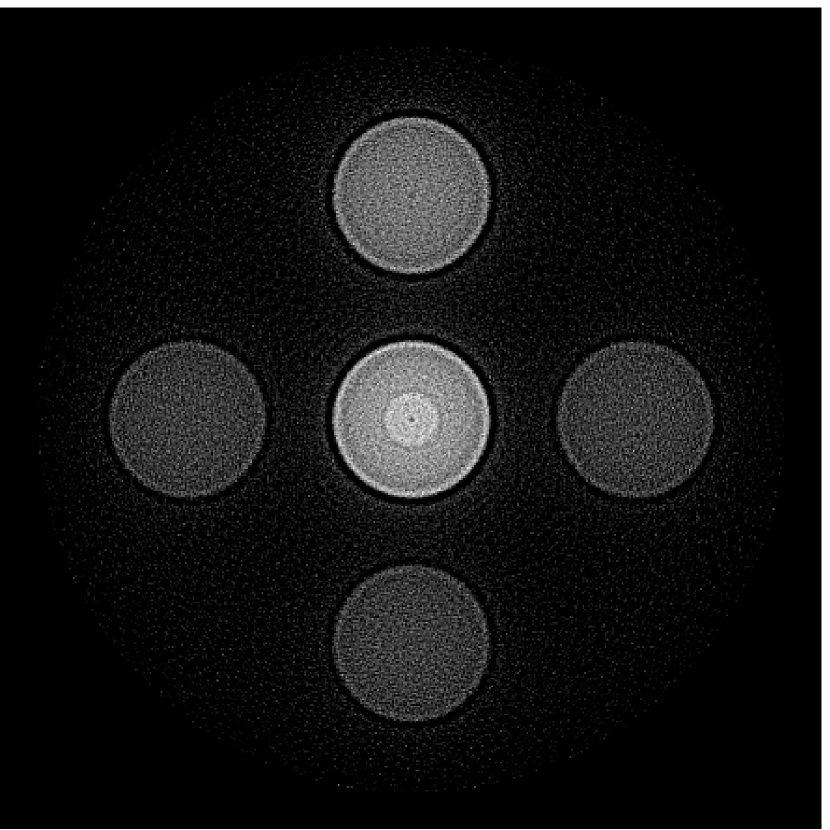

The numerical phantom shown in Figure 1(a) was employed. The phantom had a support area of mm2 and contained six uniform disks that were assigned different values of absorbed optical energy density.

A 2D circular measurement geometry was employed. transducers were evenly distributed on a ring of radius mm that enclosed the phantom. The SOS was assumed to be constant and set at mm/s. Since the simulated data were formed by use of the C-D imaging model in Eqn. (2), no inverse crime was committed. The components of this vector corresponded to equally spaced temporal samples over the interval s. Subsequently, the noiseless voltage vector was obtained by convolving the pressure data with EIR-1 in Figure 1(b).

The reconstruction region ( mm2) was represented by pixels with pixel size mm in each dimension. The initial guess of the EIR employed in the VP algorithm was different than the EIR that was assumed when generating the simulated data. This served to simulate a situation in which an experimentally measured EIR contained errors.

Each element in a real-world transducer array possesses its own EIR. In practice, the differences between the EIRs are sometimes neglected and an EIR corresponding to a single element may be used to represent all elements in the array. In some of the studies below, the EIR employed to initialize the VP algorithm (EIR-2 in Figure 1(b)) and the EIR employed to produce the simulated measurements (EIR-1 in Figure 1(b)) were experimentally measured from two different transducer elements in a circular transducer array (see Sec. VI-B). EIR-1 was measured by temporally integrating the PA signal produced by a point source positioned at the focus of the transducer. EIR-2 was measured by use of the method reported in [RNR2011]. In order to investigate the sensitivity of the VP algorithm to the initialization of the EIR, we employed different EIRs obtained by degrading EIR-1 as described later. When solving the sub-problem in Line-2 of Algorithm 1, was initialized as the zero vector. Algorithm 1 was terminated after 500 iterations, since it was observed that the changes in the reconstructed images with more iterations were negligible. When implemented by use of a single core of an Intel Xeon E5-2640 CPU, each iteration required approximately 7s to complete.

Figure 2(a) shows the image reconstructed by use of the conventional iterative method that utilized a system matrix based on EIR-2. Different values of the regularization parameter from the interval were considered. The reconstructed image with the value of that minimized the RMSE was chosen to represent the best performance of the conventional iterative method. Figure 2(a) and the profile in Figure 2(c) demonstrate that the use of an inaccurate EIR can result in strong artifacts and distortions in images reconstructed by use of the conventional methods.

When the VP algorithm was applied, different values of the regularization parameter from the interval and from the interval were considered. The image that minimized the RMSE was chosen and displayed in Figure 2(b). As revealed by this image and the profiles in 2(c), the VP algorithm yielded an image with fewer artifacts and distortions, and image fidelity was improved as reflected by the reduced RMSE.